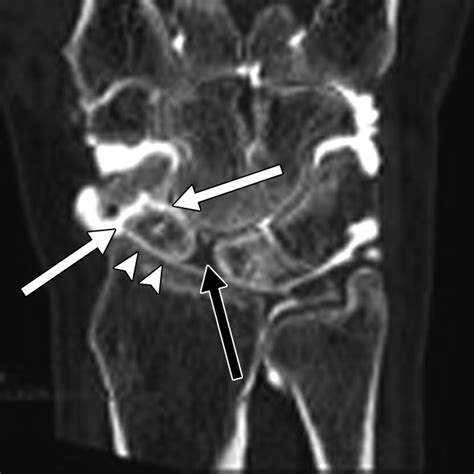

Diagnosing this condition requires a comprehensive physical examination combined with advanced imaging. Physicians typically rely on standard X-rays, which often reveal the characteristic gap in the scaphoid and the narrowing of the joint space. In more complex cases, a CT scan or MRI may be ordered to assess the exact degree of cartilage degradation and to plan potential surgical interventions.

• scaphoid nonunion advanced collapse radiology